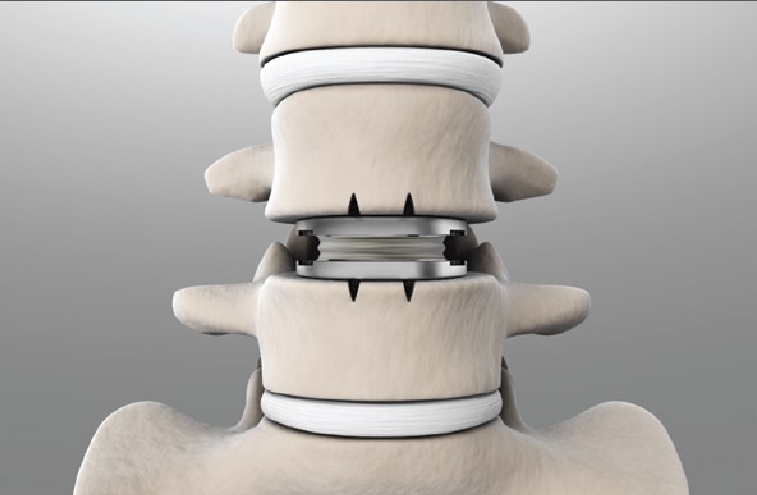

Spinal Disc Replacement

Chronic back pain or neck discomfort can significantly impact your quality of life, often